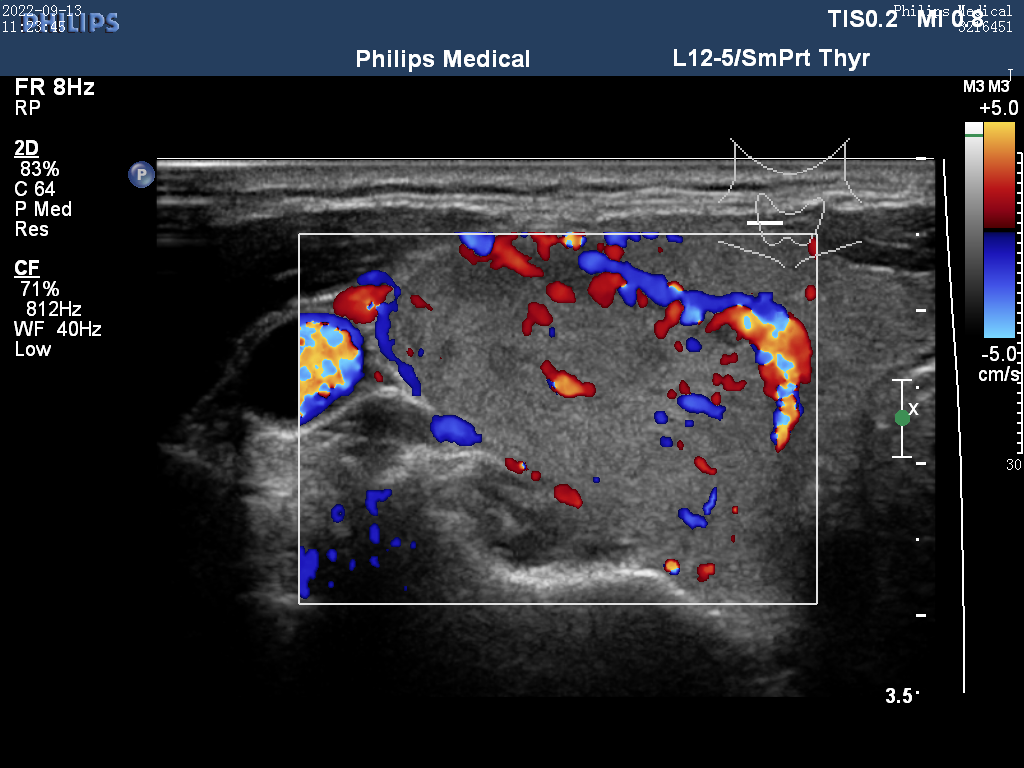

Ultrasound

ID: 29a84a37-8d70-4628-8d92-04da134d7f35...29a84a37-8d70-4628-8d92-04da134d7f35

25 yoshli Erkak

26.01.2026 09:53

Yuqori

Tashxis

Malignant (Xavfli)

Saraton xavfi aniqlandi - Zudlik bilan onkolog va endokrinolog bilan bog'laning!

Ishonch

100,0%

TSH

2,2

Tugun

0,0 sm

Yuklab olingan (13x)

Ko'rish